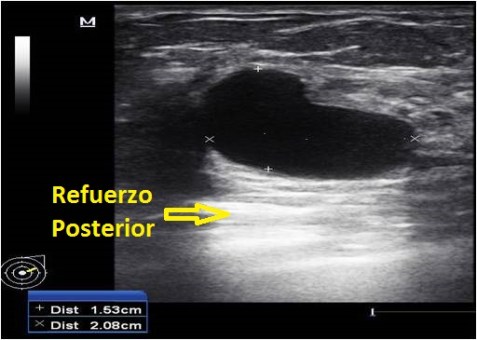

2. Refuerzo Posterior:

Se produce cuando el ultrasonido atraviesa un medio sin interfases en su interior y pasa a un medio sólido ecogénico.

Nos permite diferenciar quistes.

Permite estudiar estructuras usando como ventana estructuras llenas de líquido.

Este artefacto funciona diametralmente opuesto al anterior, ya que en vez de devolver todos los ecos del haz cuando llega a una estructura, estos ecos, en el caso de una estructura acuosa, atraviesan la estructura en un 100% prácticamente, y al llegar al tejido posterior a dicha estructura, se ve un halo hiperecogénico, es decir, más brillante, que es el Refuerzo Posterior y que responde a un paso casi total del haz de ultrasonido emitido desde nuestra sonda.

Es típico de los quistes, cuyo contenido es acuoso, y de las vejigas, y de aquellas estructuras cuyo porcentaje de agua sea muy elevado y que funcionan como ventanas para estudios de otros órganos, como el de la próstata, el útero y los ovarios, por eso decimos a los pacientes que para estudiar estas estructuras masculinas y femeninas, deben acudir a la cita con la vejiga llena.

Halo Hiperecogénico correspondiente a Refuerzo Posterior.